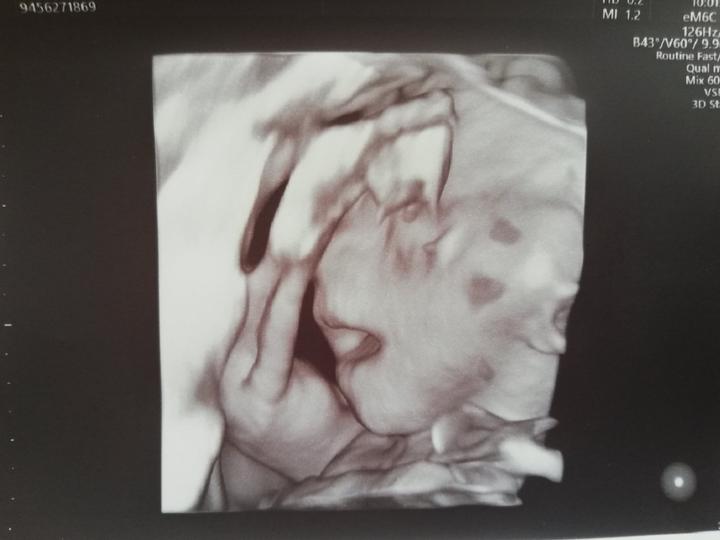

Tak ahoj, dneska jsme absolvovali velky utz a je to HOLČIČKA 😍😍😀 je zdravá a váží cca 450g, zivala a curala 😁😁 úplně živá, od dost vic než jsme takhle viděli našeho prvního😁😊takže máme páreček a přítel měl opět pravdu, že to bude to pohlaví které řekl při pohledu na první těhotenský test. 😍